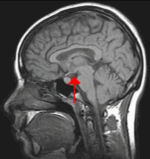

Hypotalamus – din inre törstkompass

Djupt inne i hjärnan sitter hypotalamus – kroppens egen vattenväktare. Den läser av blodets salthalt och vätskenivåer i realtid, ungefär som en känslig väderstation. Märker den att du svettats för mycket eller har låg blodvolym så skickar den en signal som översätts till en tydlig känsla: drick något – NU.